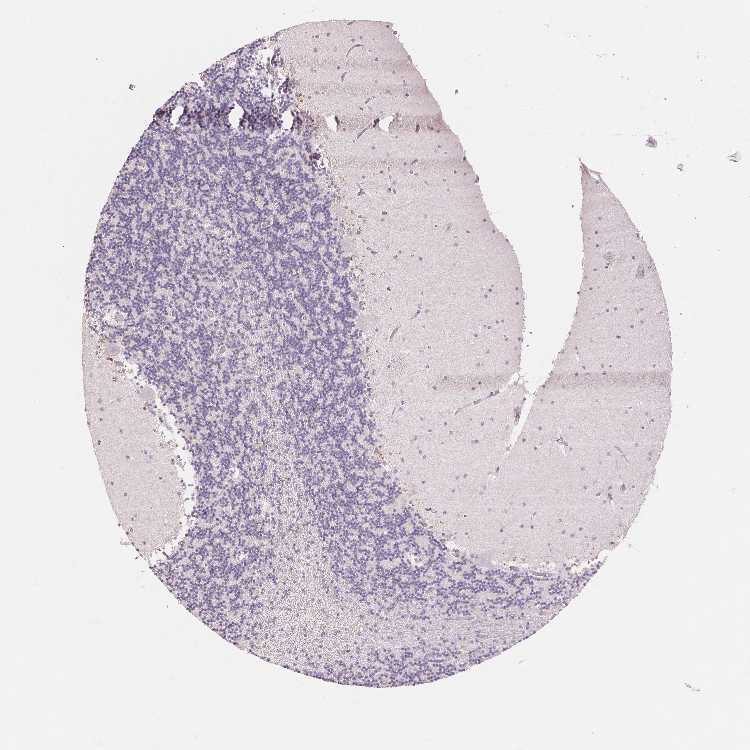

CEREBELLUM - Antibody stainingi

Antibody staining in the annotated cell types in the current human tissue is reported as not detected, low, medium, or high, based on conventional immunohistochemistry profiling in selected tissues. This score is based on the combination of the staining intensity and fraction of stained cells.

Each image is clickable and will lead to virtual microscopy that enables deeper exploration of all samples and also displays staining intensity scores, fraction scores and subcellular localization as well as patient and tissue information for each sample.

Antibody HPA051778Antibody HPA058590Antibody CAB001721

Purkinje cells Not detectedNot detectedNot detected

Cells in granular layer Not detectedMediumNot detected

Cells in molecular layer Not detectedNot detectedNot detected